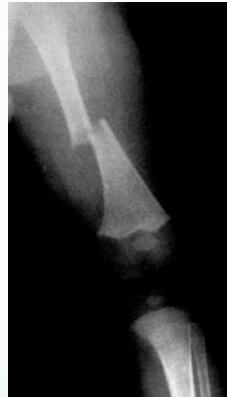

- Femur shaft fracture

- <1 year of age (70%)

- Transverse fracture

- Humeral shaft fracture

- <3 years of age

- Corner fractures (traction & rotation)

- Bucket-handle fractures (traction & rotation)

Corner Fractures:

Bucket Handle Fractures: